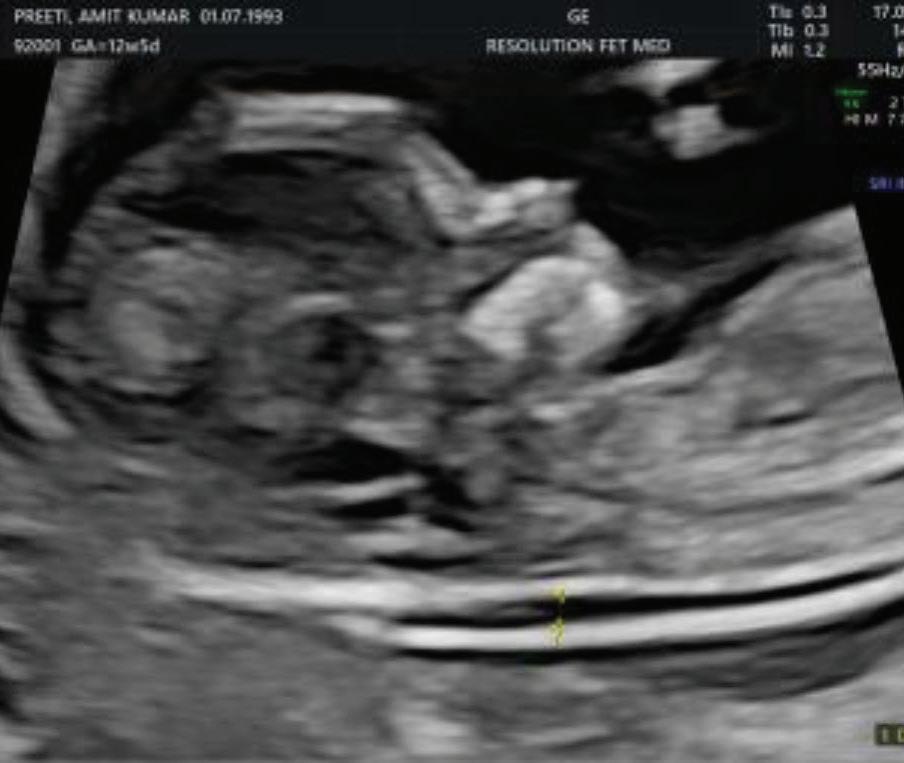

1. EARLY PREGNANCY SCAN (6–10 WEEKS)

Indications:

1. Confirmation of pregnancy.

2. location of pregnancy.

3. Number of fetus.

4. Cardiac activity.

5. Initial dating.

6. Assessment of uterine contour to ruleout any uterine anamolies.

7. Examnation of adenexa.

Findings:

• Gestational sac at ~4.5–5 weeks-Appears as anechoic fluid filled structure surrounded by a decidual reaction (Double Decidual sac sign).

• Measure Mean sac diameter .

• Yolk sac appear around ~5–5.5 weeks.

• Embryo with cardiac activity around 6 weeks.